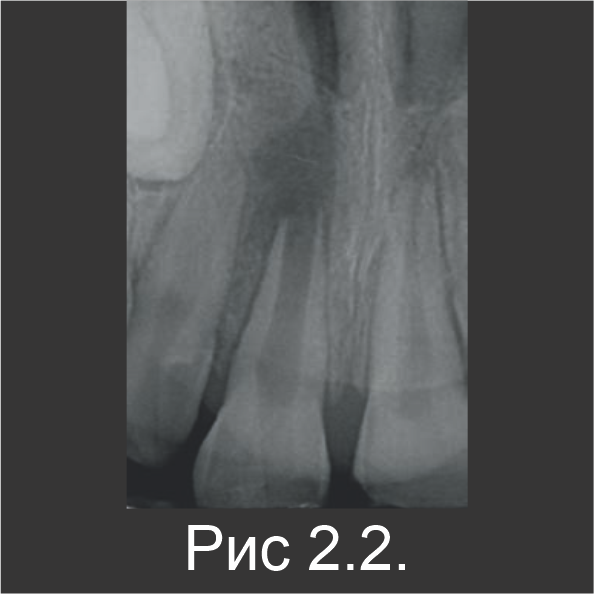

9-летнего мальчика направили на лечение инфицированного корневого канала зуба 11. За 10 месяцев до этого, т.е. в возрасте 8 лет, он перенес травму зубов, в результате которой были вывихнуты зубы 11 и 21, образовались неосложненные переломы в эмалево-дентинном соединении, а также увеличилась подвижность зубов. На оба травмированных зуба наложили шины на 2 недели, затем их восстановили с помощью композита. В ходе клинического обследования со щечной стороны зуба 11 обнаружили свищ (рис. 2.1). По рентгенограмме установили, что оба центральных резца развиваются ассиметрично, а в области апекса зуба 11 есть участок просветления (рис. 2.2).

Резец остался в несформированном состоянии (с открытым апексом), остановившись в развитии по причине некроза пульпы. В течение первого посещения резец вскрыли, после чего корневой канал промыли гипохлоритом натрия, чтобы удалить некротические ткани. Затем канал просушили и заполнили пастообразной гидроокисью кальция на 2 недели (рис. 2.3). В течение второго посещения, после удаления гидроксида кальция канал заполнили Biodentine™ (рис. 2.4).

На рентгенограмме видна перфорация Biodentine™ в зоне апекса.